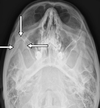

2

Q

A

left horizontal semi circular canal